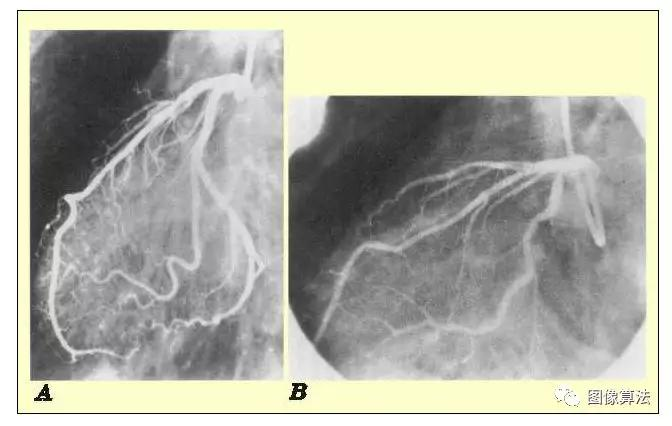

所有医学图像都包含一些视觉噪音。噪声的存在使图像具有斑驳,颗粒状,纹理或雪花的外观。下图比较了两种具有不同噪声水平的图像。我们很快就会发现,图像噪音来自各种各样的来源。没有成像方法没有噪声,但是噪声在某些类型的成像过程中比在其他类型中更普遍。

右侧图像 (B)比左侧图像噪声更大(A)